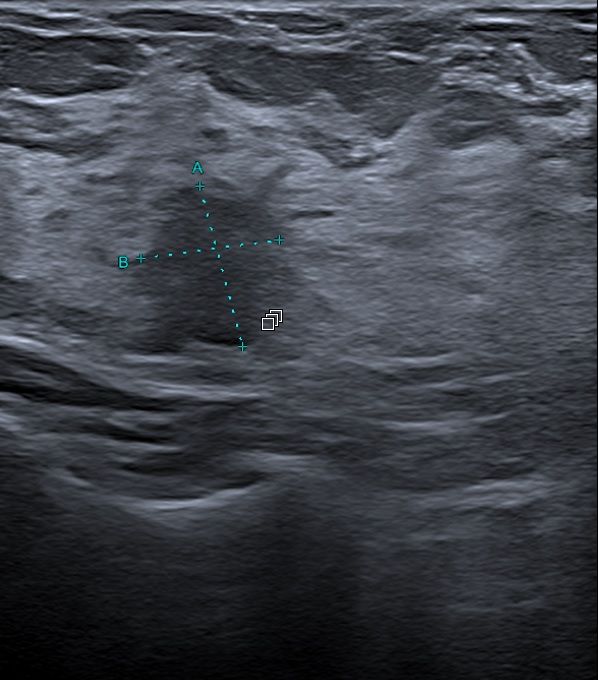

L'échographie sera l'allié idéal du radiologue dans cette opération, afin de suivre facilement l'avancée de l'aiguille et s'assurer du prélèvement sur la bonne zone de la glande mammaire.

• Il s’agit d’un prélèvement d’un fragment tissulaire réalisé sous anesthésie locale avec une aiguille pour l’analyse histologique

• Le guidage de l’aiguille suivi sur écran se fera sous échographie en position allongée

• une parfaite immobilité de votre part sera demandée pour garantir la précision millimétrique du ou des prélèvements

• Vous ne sentirez rien et entendrez simplement un déclic dû au déplacement de l’aiguille dans le boitier